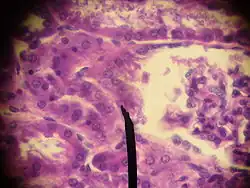

Juxtaglomerulární buňky mají oválná jádra a cytoplazmu naplněnou granuly, které se barví metodou PAS. V elektronovém mikroskopu mají JG buňky charakter elementů vylučujících proteiny a obsahují množství drsného endoplazmatického retikula, znamenitě vyvinutý Golgiho komplex a sekreční granula o průměru 10-40 nm.